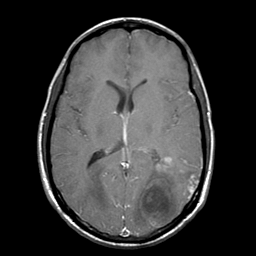

Sarcoma, MR Study #1 mr-gad -- Slice #12

[Home][Help][Clinical] Slice 12